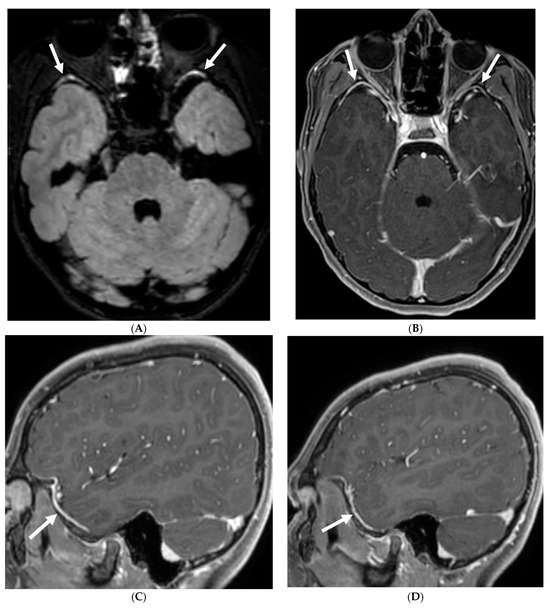

Figure 22.

Post contrast axial FLAIR (A), axial T1 FS (B), sagittal T1 Right (C) and Left (D): 10-year-old girl with elevated ANCA, headache and mild LUE weakness. There is bilateral anterior temporal smooth dural enhancement (white arrows). Diagnosis: Antineutrophilic cytoplasmic antibody (ANCA) associated vasculitis, likely granulomatosis with polyangiitis.